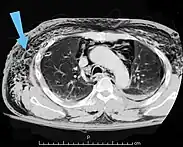

An abdominal CT scan of a patient with subcutaneous emphysema (arrows)

Significant cases of subcutaneous emphysema are easy to diagnose because of the characteristic signs of the condition.[1] In some cases, the signs are subtle, making diagnosis more difficult.[13] Medical imaging is used to diagnose the condition or confirm a diagnosis made using clinical signs. On a chest radiograph, subcutaneous emphysema may be seen as radiolucent striations in the pattern expected from the pectoralis major muscle group. Air in the subcutaneous tissues may interfere with radiography of the chest, potentially obscuring serious conditions such as pneumothorax.[18] It can also reduce the effectiveness of chest ultrasound.[27] On the other hand, since subcutaneous emphysema may become apparent in chest X-rays before a pneumothorax does, its presence may be used to infer that of the latter injury.[13] Subcutaneous emphysema can also be seen in CT scans, with the air pockets appearing as dark areas. CT scanning is so sensitive that it commonly makes it possible to find the exact spot from which air is entering the soft tissues.[13] In 1944, M.T. Macklin and C.C. Macklin published further insights into the pathophysiology of spontaneous Macklin's Syndrome occurring as a result of a severe asthmatic attack.